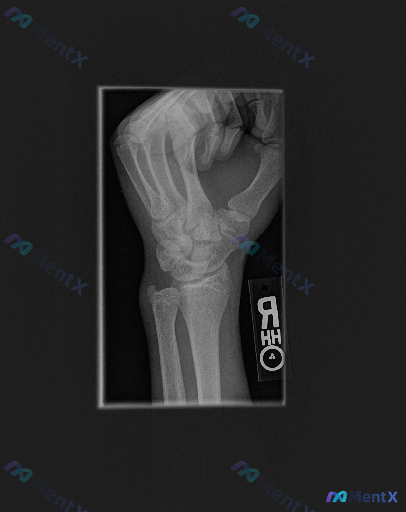

这张青少年右腕斜位X光片,你会关注到什么?

整理到一份影像资料,大家一起看看。 基本背景: 右侧手腕部斜位X光片,提示患者处于骨骼发育期。 影像表现: 1. 投照为右腕关节斜位,第一掌骨基底部与大多角骨间隙可见,但腕骨间重叠较明显,部分细节遮挡; 2. 腕关节周围软组织轮廓清晰,未见明显局限性肿胀、皮下气肿或异物; 3. 舟骨中部可见,未见明...